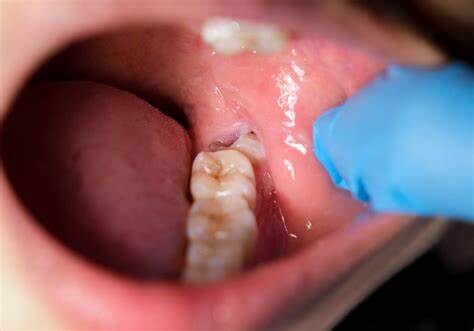

Formation of Cysts or Tumours

If the wisdom teeth problems are not dealt in an appropriate manner, the tooth will develop a sac within the jawbone. This sac has the ability to fill with fluid, which gradually develops into the formation of cyst, damaging the teeth, jawbone, and nerves. There are chances that this cyst could progressively develop into a tumour if untreated which could ultimately result in the removal of tissue and jaw bones.